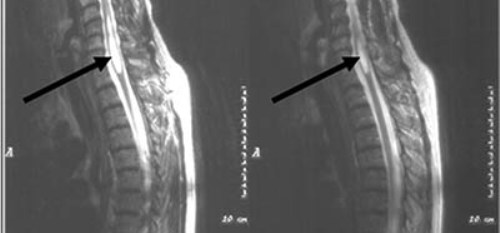

магнитно-резонансная томография позволяет визуализировать спинной мозг и выявить локализацию поражения;